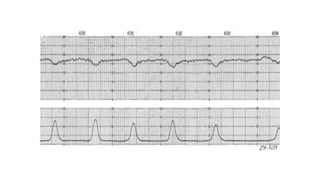

RCTG

Evalúa la relación que guardan las aceleraciones y

desaceleraciones en la línea de base de la frecuencia

cardíaca fetal en relación a estímulos de diversa

ìndole

El principal problema radica en la identificar patrones

relacionados con la hipoxia y por consiguiente,

intervenciones en ocasiones innecesarias en muchos

partos en un intento de prevenir la hipoxia

intrapartum.

Parámetros A Evaluar RCTG

Línea de base:

FCF cuando esta es estable, durante una ventana de 10 minutos, excluye

aceleraciones, deceleraciones y períodos de variabilidad marcada (>25 latidos por

minuto (lpm).

Al menos visualizar segmentos de 2 minutos.

Fluctuaciones en la FCF de la línea de base que son

irregulares en amplitud y frecuencia.

Podría ser:

Ausente: amplitud indetectable

Mínima: amplitud que varía entre > de indetectable y ≤ 5

lpm

Moderada: amplitud entre 6 lpm y 25 lpm NORMAL

Marcada: amplitud > 25 lpm

Variabilidad: